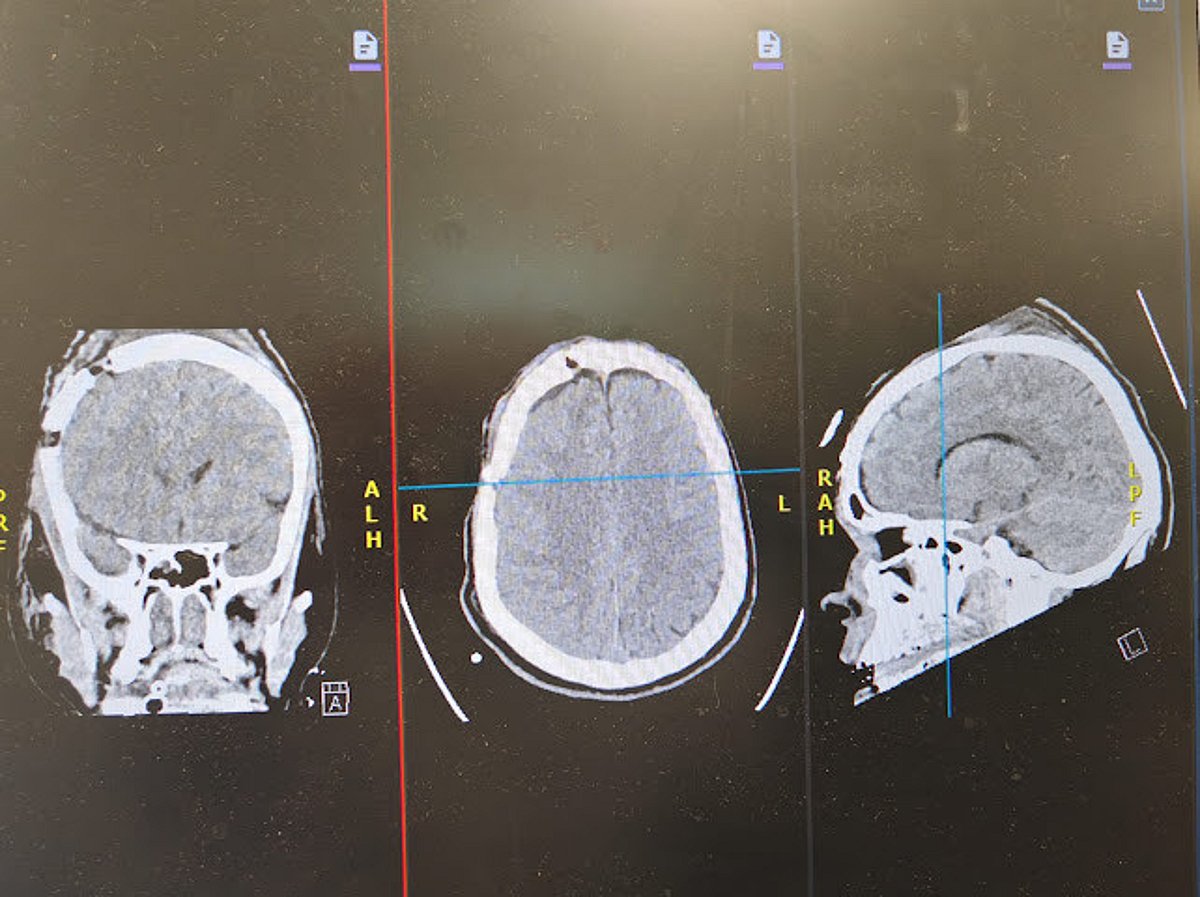

نجح فريق طبي متخصص في مستشفى الأمير عبدالمحسن بمحافظة العلا، أحد مكونات تجمع المدينة المنورة الصحي، في إنقاذ حياة شاب يبلغ من العمر 26 عامًا، تعرّض لإصابات بالغة جراء حادث مروري أسفر عن نزيف حاد في الدماغ وكسور متعددة.